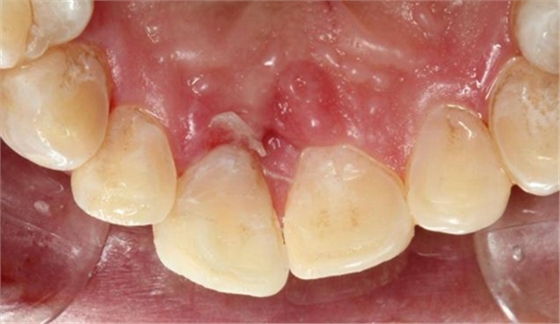

第二日復(fù)查,給予樹(shù)脂恢復(fù)A2A1B1切斷缺損。術(shù)后如下圖:

術(shù)后即刻如下圖:

術(shù)后5小時(shí)復(fù)查如下圖: